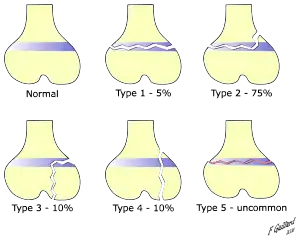

There are nine types of Salter–Harris fractures; types I to V as described by Robert B Salter and W Robert Harris in 1963,[3] and the rarer types VI to IX which have been added subsequently:[5]

- Type I – transverse fracture through the growth plate (also referred to as the "physis"):[6] 6% incidence

- Type II – A fracture through the growth plate and the metaphysis, sparing the epiphysis:[7] 75% incidence, takes approximately 12-90 weeks or more in the spine to heal.[8]

- Type III – A fracture through growth plate and epiphysis, sparing the metaphysis:[9] 8% incidence

- Type IV – A fracture through all three elements of the bone, the growth plate, metaphysis, and epiphysis:[10] 10% incidence

- Type V – A compression fracture of the growth plate (resulting in a decrease in the perceived space between the epiphysis and metaphysis on x-ray):[11] 1% incidence